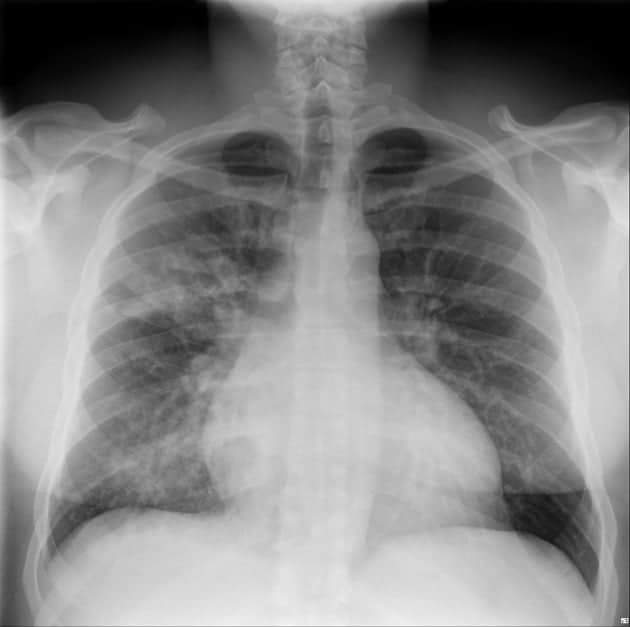

TANDA PARU-PARU ANDA TERKENA PENYAKIT INFEKSI PNEUMONIA, KENALI CIRI-CIRINYA! (BAGIAN 1)

๐—ง๐—”๐—ก๐——๐—” ๐—ฃ๐—”๐—ฅ๐—จ-๐—ฃ๐—”๐—ฅ๐—จ ๐—”๐—ก๐——๐—” ๐—ง๐—˜๐—ฅ๐—ž๐—˜๐—ก๐—” ๐—ฃ๐—˜๐—ก๐—ฌ๐—”๐—ž๐—œ๐—ง ๐—œ๐—ก๐—™๐—˜๐—ž๐—ฆ๐—œ ๐—ฃ๐—ก๐—˜๐—จ๐— ๐—ข๐—ก๐—œ๐—”, ๐—ž๐—˜๐—ก๐—”๐—Ÿ๐—œ ๐—–๐—œ๐—ฅ๐—œ-๐—–๐—œ๐—ฅ๐—œ๐—ก๐—ฌ๐—”! ๐—ฃ๐—ก๐—˜๐—จ๐— ๐—ข๐—ก๐—œ๐—” merupakan penyakit infeksi paru yang disebabkan oleh virus, bakteri atau jamur. Dimana akibat infeksi tersebut ... Selengkapnya